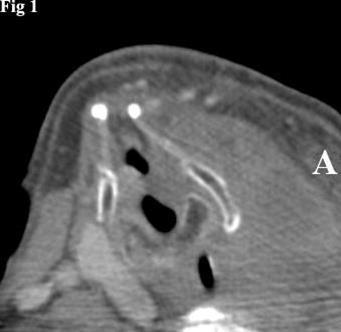

Figure 1.CT image of left thyroid lobe tumor causing rightward displacement of the laryngeal structures. The mass has a homogeneous appearance.

Computed tomography showed a mass, measuring 8x5x7 cm, unevenly distributed in the left thyroid lobe and the presence of colloid cysts and calcified nodules. The mass was causing compression and lateral displacement of the trachea and esophagus with no apparent signs of infiltration of these structures (Figure 1).